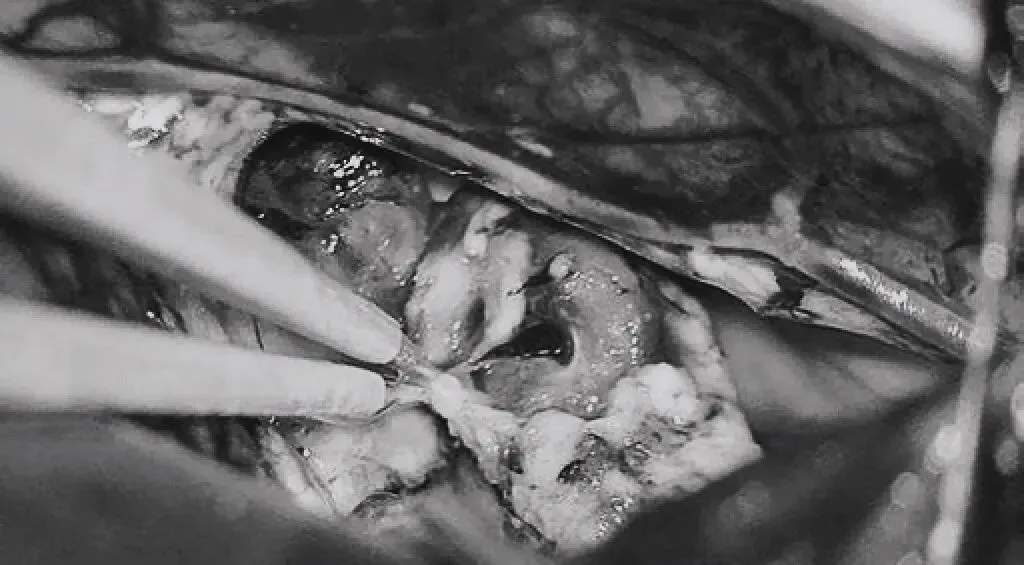

引流静脉进入ICV处电凝。完全切除AVM。

每一步都在毫米之间博弈,每一刀都是技术与经验的极致考验。